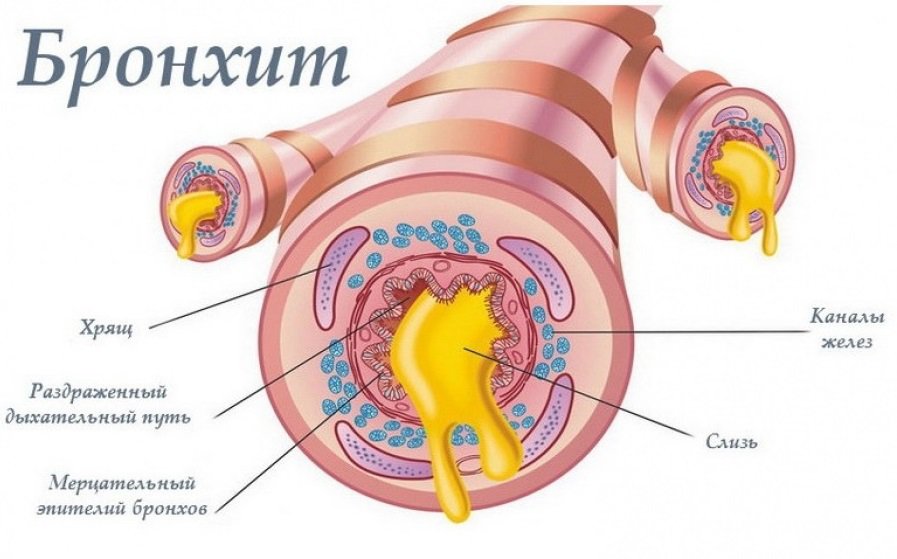

Бронхит у детей – это диффузное воспалительное заболевание бронхов, при котором поражается слизистая оболочка или вся толща стенки бронхов. Заболевание может возникать изолированно или развиваться на фоне других патологических процессов. Бронхиты у детей относятся к наиболее распространенным заболеваниям респираторного тракта, бронхолегочная патология у детей развивается чаще, а также может иметь более тяжелое течение, чем у взрослых пациентов. Обструктивная форма бронхита регистрируется примерно у 20% детей первых лет жизни.